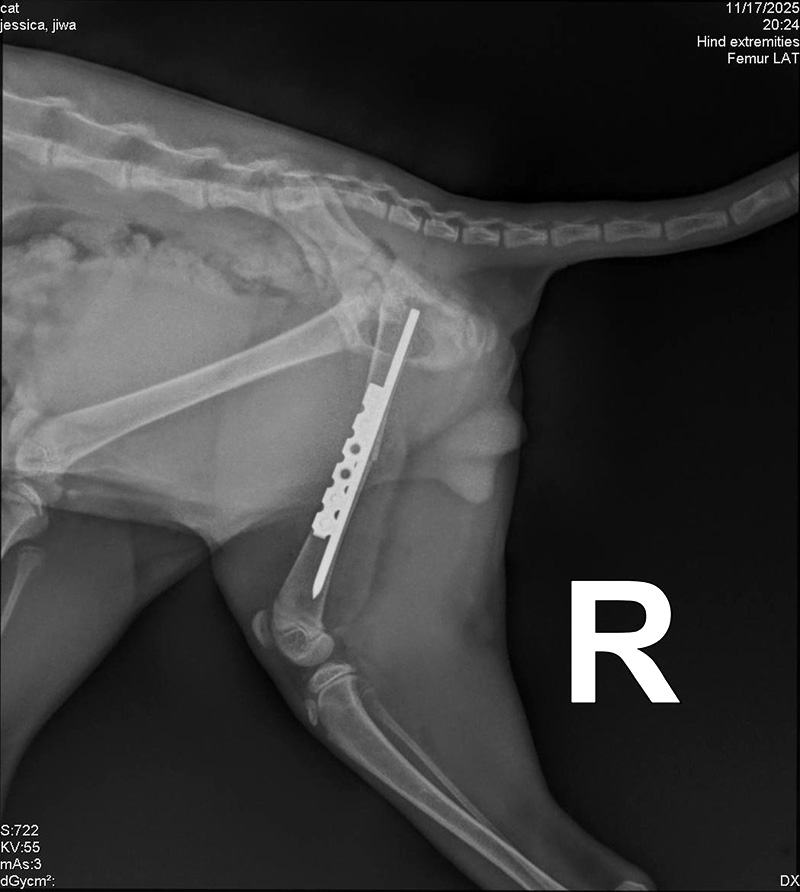

- Hasil rontgen menunjukkan tulang pahanya patah sehingga harus dioperasi. Namun, tantangannya adalah kucing hutan sulit dikendalikan dan sangat sensitif manusia.

Kadek Agus Arnawa (41), dokter hewan di Central Vet Bali, mengatakan penanganan dilakukan melalui prosedur medis ketat. Mulai dari pemeriksaan awal, penetapan diagnosis patah tulang, tindakan operasi pemasangan pen, hingga pemulihan dengan kontak seminimal mungkin untuk mencegah setres.

Hasil rontgen menunjukkan tulang pahanya patah sehingga harus segera dioperasi. Namun, tantangannya adalah kucing hutan sulit dikendalikan dan sangat sensitif manusia.

Di kasus satwa kecil seperti kucing hutan muda ini, pemasangan implasi harus hati-hati agar tidak mengganggu growth plate (gerut pelit), area pertumbuhan tulang.

“Kalau semuanya lancar, tulangnya akan sembuh dalam enam minggu,” jelas Kadek.